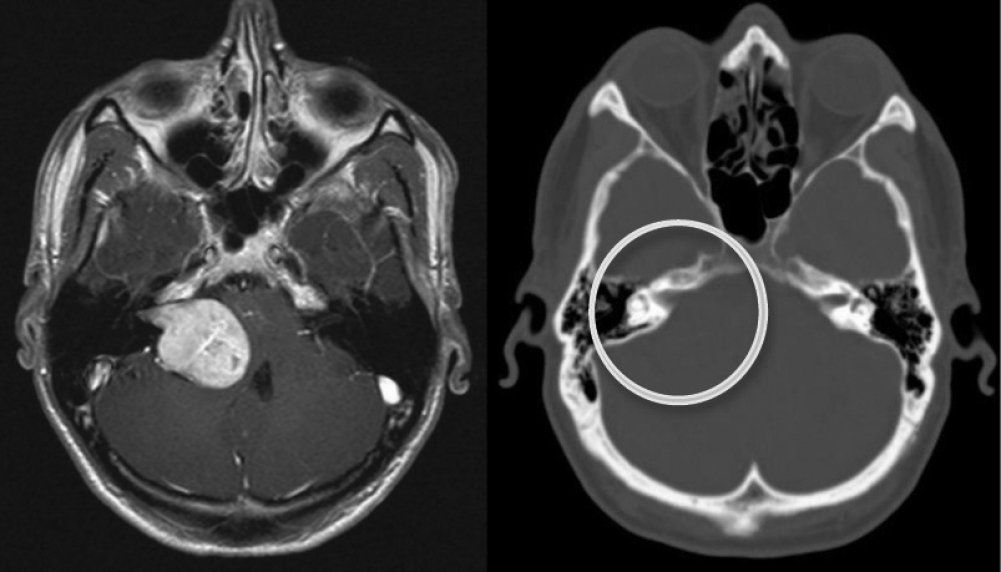

- Магнитно-резонансная томография (МРТ). Это золотой стандарт в диагностике опухолей мозга. МРТ с контрастным усилением позволяет детально визуализировать новообразование, определить его размеры, точное расположение и отношение к важным структурам мозга. Контрастное вещество накапливается в участках с нарушенным гематоэнцефалическим барьером, что характерно для многих опухолей.